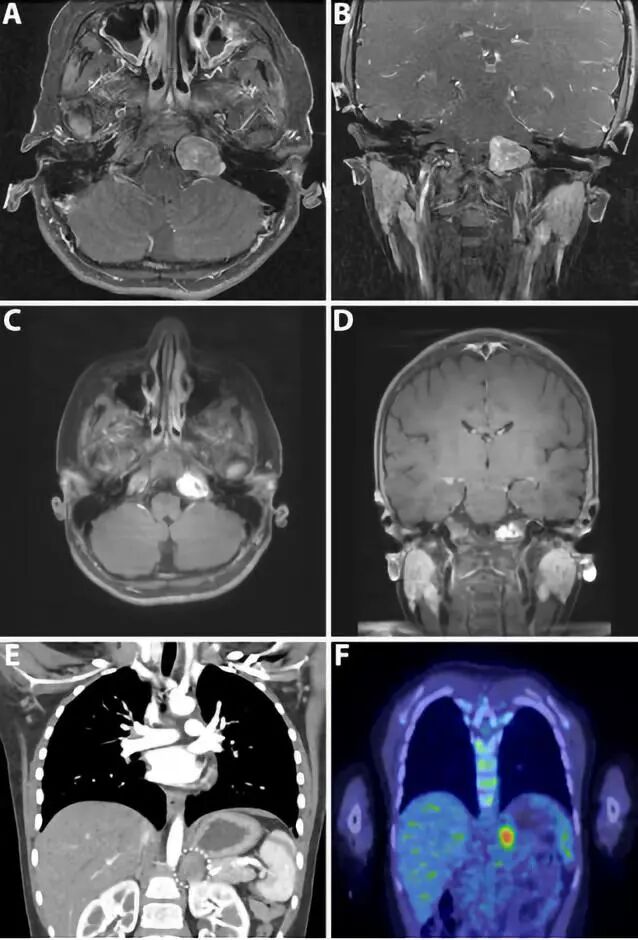

4.儿童未确诊大脑动静脉畸形引起的急性致命性脑出血:单中心回顾性研究

Acute fatal hemorrhage from previously undiagnosed cerebral arteriovenous malformations in children: a single-center experience.

DOI: 10.3171/2018.3.PEDS1825.

动静脉畸形(AVM)引起的脑出血最严重的并发症就是死亡,该单中心研究分析之前未确诊的AVM出血致突发死亡的发生率,明确相关的临床和影像学因素。作者回顾分析了2006-2017年间之前未确诊的AVM首次颅内出血的57位患者,平均年龄10.8岁。其中7位(12%)患儿(平均年龄11.5岁)的脑出血导致死亡,死亡患儿罹患后颅窝AVM的概率是存活患儿的4倍,未发现明显的诱发因素(如剧烈运动、外伤等),死亡的7例患儿中3例在入院前出现过心脏骤停。42/50例(84%)存活的患儿最后行AVM切除术,这些数据说明积极主动的处理儿童动静脉畸形是非常必要的。

![]()

左侧小脑半球AVM突发出血致患儿死亡